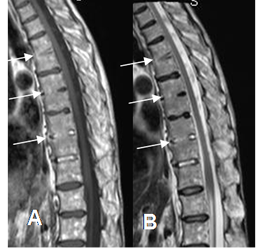

A: RM sagital en T1 y B: RM sagital en T2. Formación de sindesmofitos, que produce fusión entre los cuerpos vertebrales dorsales.